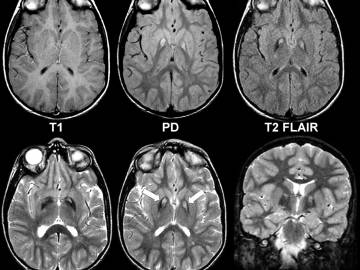

Магнитно-резонансная томография позволяет визуализировать всевозможные участки человеческого тела и незаменима во многих случаях в диагностике неврологических заболеваний, а вот как часто можно делать МРТ, мы поговорим в этой статье. МРТ и МСКТ диагностика (компьютерная томография) - это разные по своим физическим принципам исследования. Но при этом данные виды томографии могут оценить состояние и структуру органа в данный момент. Чтобы проследить динамику необходимо проведение повторного исследования. Напрашивается вопрос: так как же часто нужно делать повторное МРТ исследование? Для этого рассмотрим раздельно МРТ диагностику различных заболеваний головного мозга. Как часто можно делать МРТ без вреда Любое МРТ можно делать без вреда для здоровья неограниченное количество раз, поскольку магнитно-резонансное обследование не несет в себе никакой лучевой нагрузки в отличие от компьютерной томографии, где применяется рентген, и доза облучения доходит до 10 мЗв за одно сканирование. Из-за т

Магнитно-резонансная томография позволяет визуализировать всевозможные участки человеческого тела и незаменима во многих случаях в диагностике неврологических заболеваний, а вот как часто можно делать МРТ, мы поговорим в этой статье. МРТ и МСКТ диагностика (компьютерная томография) - это разные по своим физическим принципам исследования. Но при этом данные виды томографии могут оценить состояние и структуру органа в данный момент. Чтобы проследить динамику необходимо проведение повторного исследования. Напрашивается вопрос: так как же часто нужно делать повторное МРТ исследование? Для этого рассмотрим раздельно МРТ диагностику различных заболеваний головного мозга.

Для правильной диагностики рассеянного склероза важна нейровизуализация, чтобы выяснить, есть ли очаги демиелинизации. Для этого проводят первичную МРТ головного мозга с контрастом. Вторым шагом является оценка динамических изменений. Для этого необходимо сделать повторную МРТ через 6-12 месяцев. В ходе этого исследования врач ищет признаки изменения очагов - при прогрессирующем рассеянном склерозе имеющиеся очаги, как правило, увеличиваются или добавляются новые. На этапе лечения контроль состояния очагов через томографию имеет смысл проводить 1 раз в год.